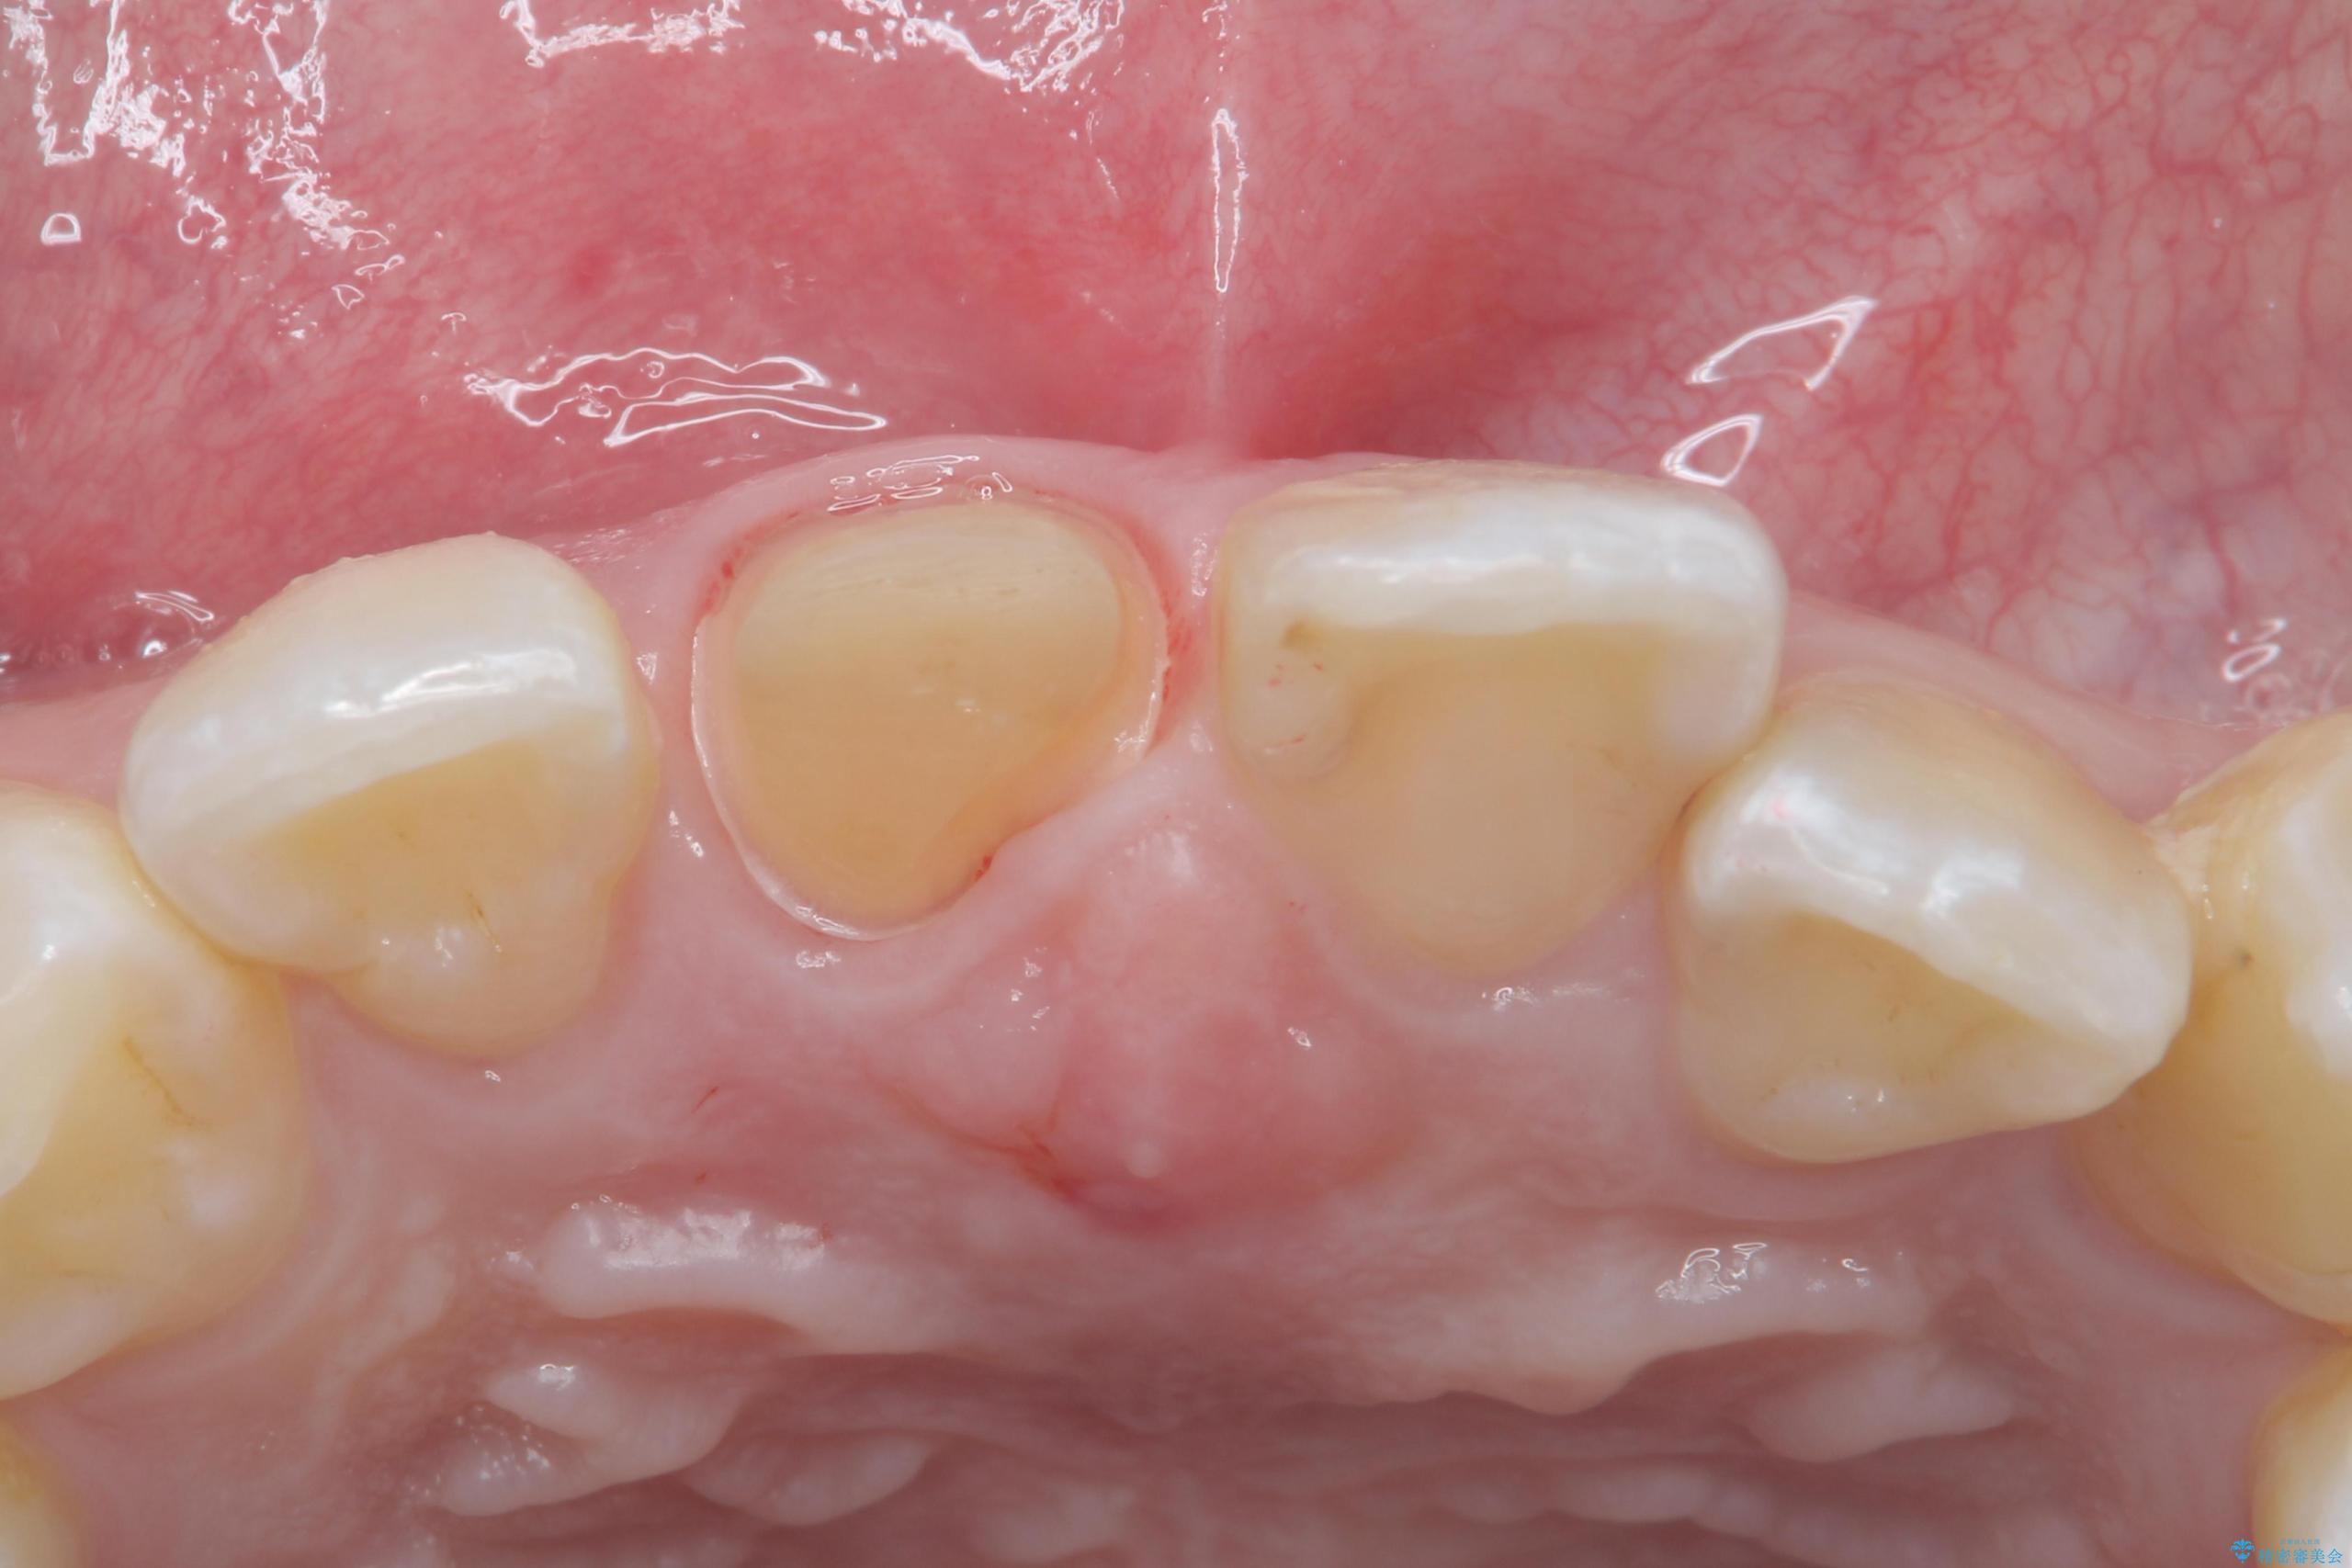

- 前歯のかぶせ物の色が気になるとのことで来院された患者様です。

セラミッククラウンで作り変えていきます。